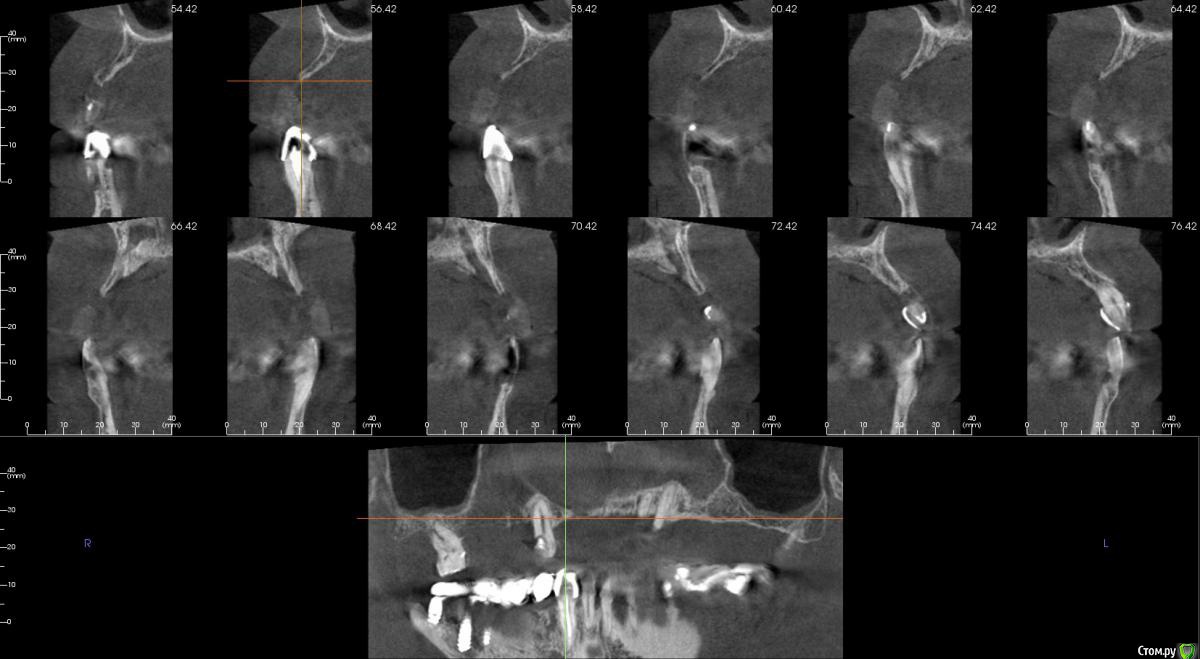

kamranchick Опубликовано 20 сентября, 2016 Поделиться Опубликовано 20 сентября, 2016 Интересует сторона 2. там хочу сделать соссидж, через несколько месяцев сделать закрытый синус и установить 2 винта в области 14 и 16, как вы думаете?и можно ли сделать конструкцию не брав во внимание фронтальный отдел? пациент финансово не тянет фронт Ссылка на комментарий

kamranchick Опубликовано 20 сентября, 2016 Автор Поделиться Опубликовано 20 сентября, 2016 Может убрать всё и на 4 ёх конструкцию предложить?думаю не получится, так как придется аугментировать и фронтальный отдел и боковой отдел чтобы по хорошему сделать все на 4, тем более я работаю на Осстем, а у нас мультиков в системе нет Ссылка на комментарий

колесников Опубликовано 20 сентября, 2016 Поделиться Опубликовано 20 сентября, 2016 думаю не получится, так как придется аугментировать и фронтальный отдел и боковой отдел чтобы по хорошему сделать все на 4, тем более я работаю на Осстем, а у нас мультиков в системе нетНе нужно там ничего аугментировать. Меняете корни на импланты. В обл премоляров так же есть объём по снимку. Иначе череда костных и мягкотканных пластик с неясным прогнозом. Пациент точно не потянет. У остема платформа 4.0 совместима с астровской 4.5-5.0. Можно у астры взять запчасти. Ссылка на комментарий